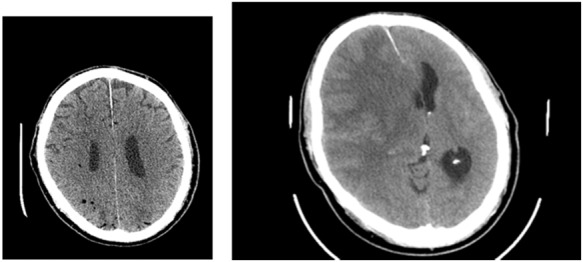

Figure 1.

A: fluid-gas interface (white arrow), B: bubbles after ABC manoeuvre (white arrows).